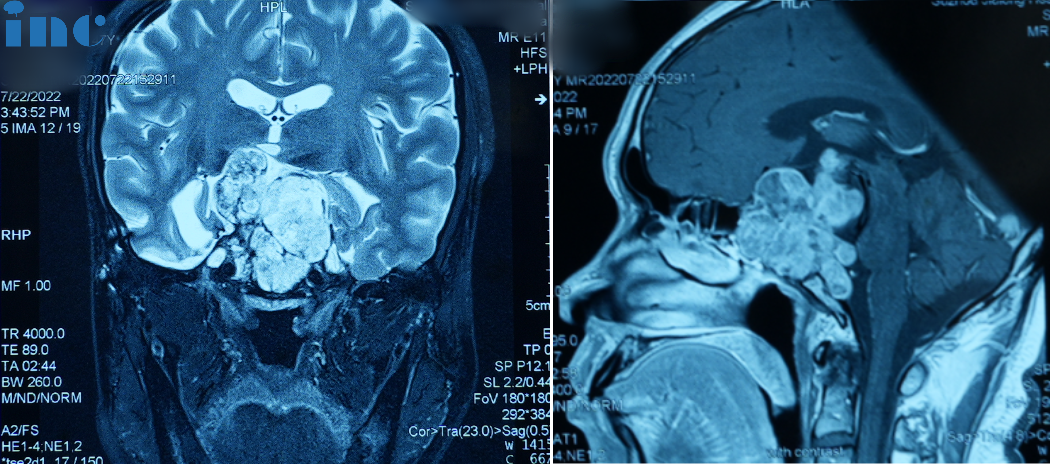

較大脊索瘤復(fù)發(fā)真實(shí)案例圖片

脊索瘤復(fù)發(fā)圖片

2022年7月,患者三次出現(xiàn)視力下降/視野缺損癥狀,磁共振檢查再次提示“鞍區(qū)腫瘤復(fù)發(fā)”。

經(jīng)鼻內(nèi)鏡手術(shù)圖片

經(jīng)鼻內(nèi)鏡手術(shù)圖片1

因患者不想再接受開顱手術(shù),10月8日全麻下行經(jīng)鼻神經(jīng)內(nèi)鏡下腫瘤切除術(shù)。術(shù)后病理為“脊索瘤(復(fù)發(fā))”。術(shù)后出現(xiàn)嗜睡、精神萎靡等內(nèi)分泌功能紊亂癥狀,同時(shí)伴腦積水。遂于11月19日行腦脊液V-P分流術(shù),后癥狀緩解消失。

經(jīng)鼻內(nèi)鏡手術(shù)圖片2